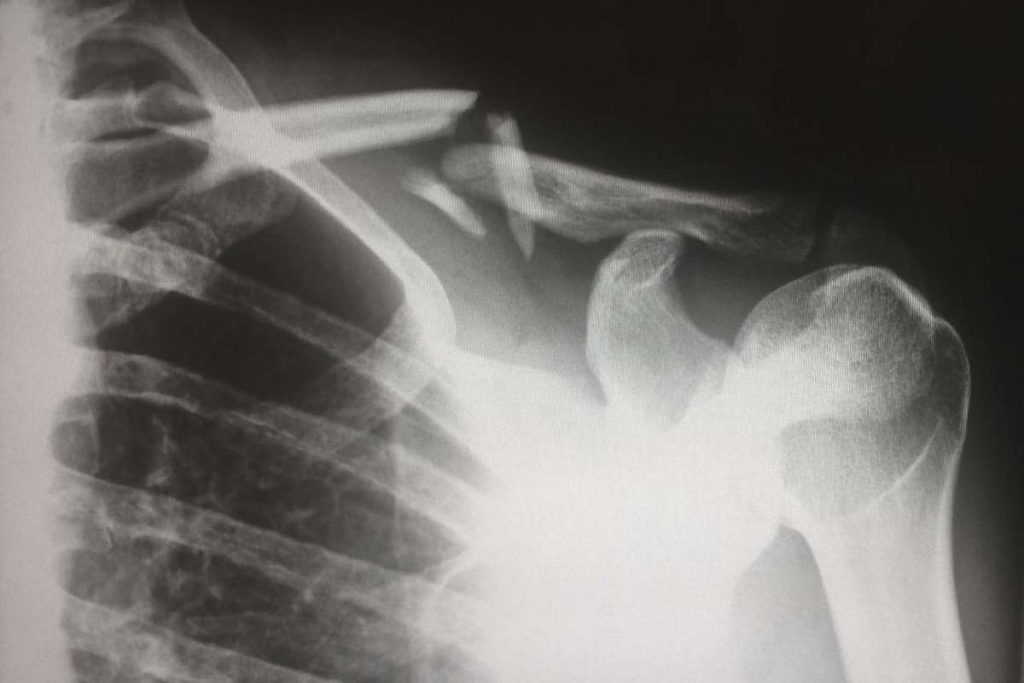

• Les fractures osseuses causées par un accident ou une maladie

Pour les individus ayant subi un accident ou une blessure traumatique, comme une fracture osseuse sévère ou une entorse grave, la chirurgie orthopédique peut être nécessaire pour faciliter la guérison et prévenir d’éventuelles complications. Par exemple, le placement d’une vis ou d’une plaque peut s’avérer crucial pour assurer la consolidation correcte d’un os fracturé.